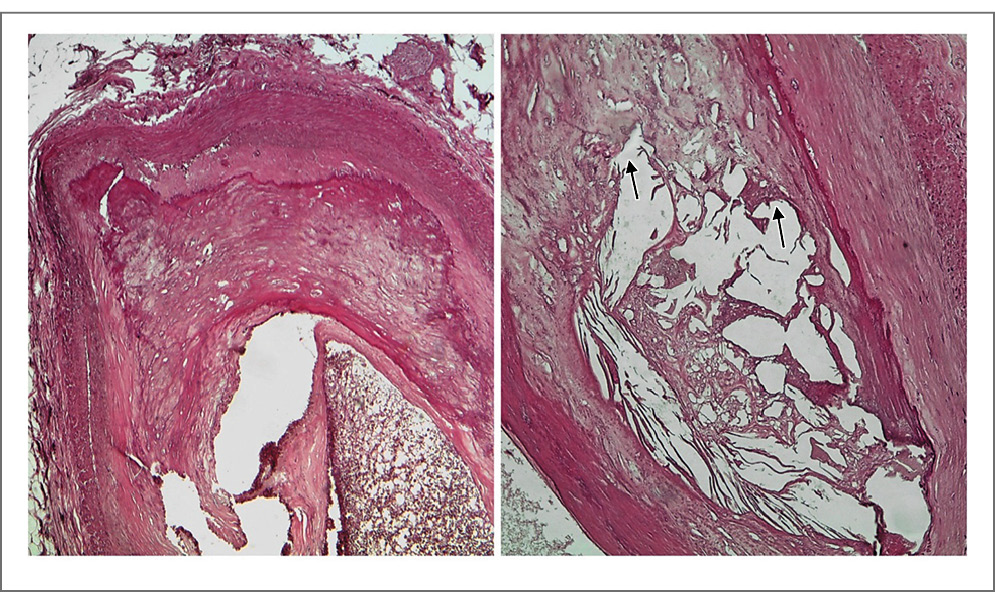

Рис. 6. Микрофотография левой КА у пациента с ИМ 2-го типа. Морфологические признаки выраженного атеросклероза с атероматозом и атерокальцинозом (стрелки), просвет артерии уменьшен более чем наполовину. Окраска гематоксилином и эозином, ×40 (слева) и ×100 (справа).